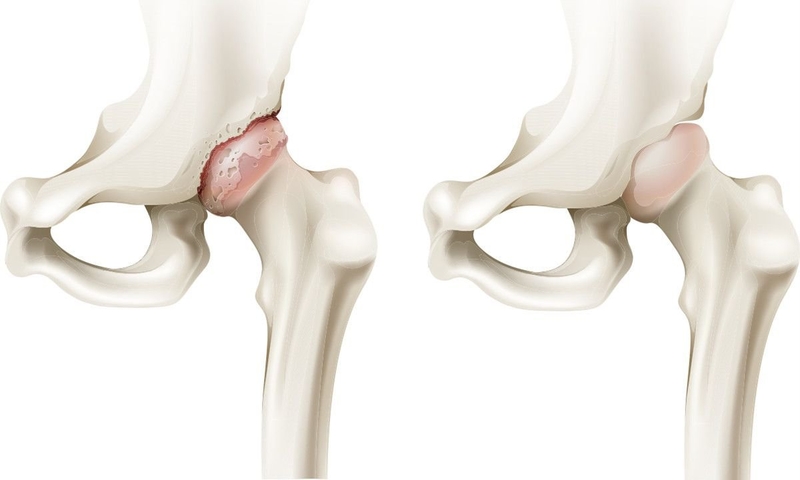

Sinh lý bệnh dẹt chỏm xương đùi ở trẻ em và người lớn đều giống nhau. Bệnh được đặc trưng bởi quá trình tự hủy của các tế bào xương - tủy xương và các tế bào hình thành xương - dẫn đến sự sụp đổ của đầu với tổn thương tiếp theo của sụn nằm phía trên, và do đó làm phẳng hình dạng bề mặt tròn của đầu khớp với ổ cối, cuối cùng, gây ra, viêm xương khớp thứ phát.

Thiếu máu có thể phá hủy xương và làm chúng biến dạng vĩnh viễn. Những bóng nằm trên đầu xương đùi và vừa khít với khớp hông, trong tình trạng này, nguồn cung cấp máu cho bóng bị cắt và xương sẽ chết. Phần bị ảnh hưởng của xương đùi trở nên dẹt, biến dạng và có nguy cơ bị bong ra khỏi khớp hông. Lớp sụn hỗ trợ các đầu xương biến mất khiến chúng bị bong ra và gãy.